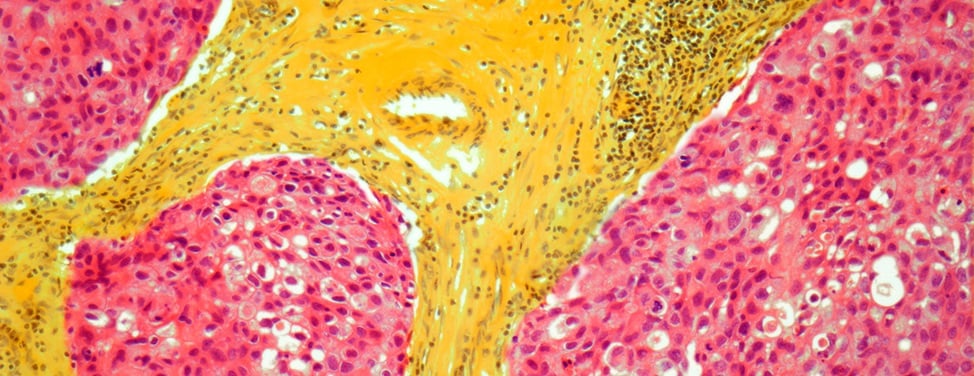

Biopsy for breast cancer

A biopsy may be used to determine whether a breast lump or other abnormal tissue is cancer. During a biopsy, a surgeon, pathologist or radiologist removes a portion or all of the suspicious tissue. The tissue is then examined under a microscope by a pathologist, who checks for cancer cells and makes the diagnosis.

When cancer cells form in the ducts or milk lobules and spread to the breast tissue around them, the cancer is considered invasive. Tumors can be found during a breast exam or through screening tests, such as a mammogram. The severity of the cancer and best course of treatment depend on the tumor's size, what the cells look like under a microscope, and whether the cancer has spread to lymph nodes (small, bean-shaped structures that are part of the body's immune system).